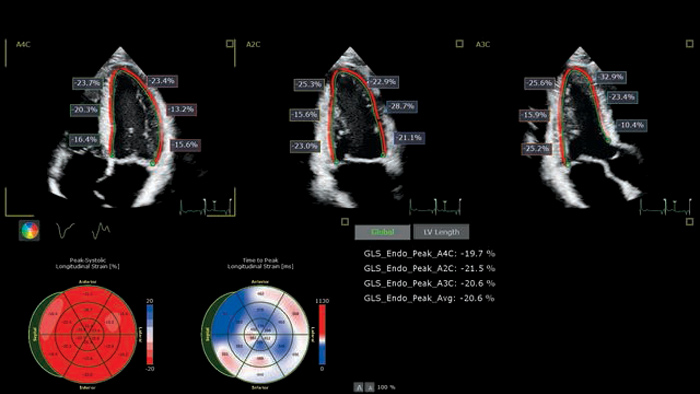

Dr. Roberto Lang, University of Chicago, Chicago, Illinois USA

Cardiac implications of COVID-19

Automated strain tools can simplify assessment of right ventricular function, impacting care pathways of patients with COVID-19.

Dr. Teresa Lopez-Fernandez, La Paz University Hospital, Madrid, Spain

Using advanced ultrasound tools to assess CTRCD

Time-consuming methods are overcome by applying Philips Anatomically Intelligent Ultrasound (AIUS) to cardiotoxicity prevention.